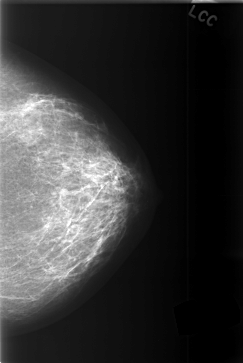

C_0374_1.LEFT_CC

LEFT_CC LINES 5808 PIXELS_PER_LINE 3880 BITS_PER_PIXEL 12 RESOLUTION 50 NON_OVERLAY